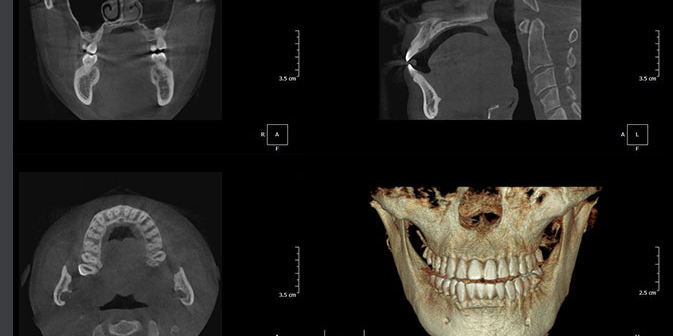

More detail, more confidence

70μm resolution @ 4x3cm

Image reconstruction in 6 seconds

Superior image processing technology